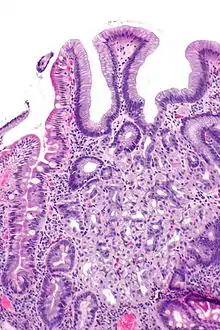

In medicine, heterotopia is the presence of a particular tissue type at a non-physiological site, but usually co-existing with original tissue in its correct anatomical location. In other words, it implies ectopic tissue, in addition to retention of the original tissue type.

In neuropathology, for example, gray matter heterotopia is the presence of gray matter within the cerebral white matter or ventricles. Heterotopia within the brain is often divided into three groups: subependymal heterotopia, focal cortical heterotopia and band heterotopia. Another example is a Meckel's diverticulum, which may contain heterotopic gastric or pancreatic tissue.